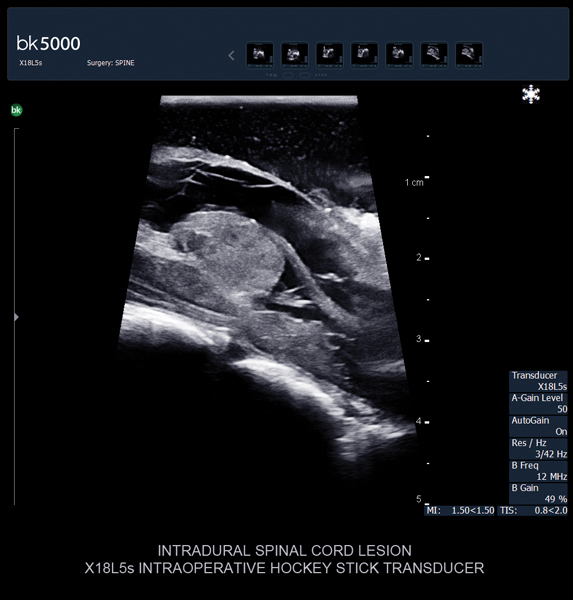

Ultrasound can improve neurosurgical procedures by helping you navigate and identify lesions and anatomical structures in real-time. This is particularly important as the data obtained from a preoperative CT or MRI scan can be outdated at the time of surgery. The bk5000 neurosurgical system provides the highest quality images that allow you to clearly see the margins of a lesion and to determine the best course of action. Using advanced graphics processing technology, this powerful system provides immediate, auto-optimized images that allow you to see the information you need, faster.

Transducers designed for Neurosurgery

The specialized, high-resolution, sterilizable neurosurgery transducers enable you to obtain detailed images of the brain and spinal cord. They have a convenient Smart™ button that lets you activate the transducer, then freeze, store or print the images at the press of a button. Disposable, easy-to-use needle guides assist with targeting lesions.